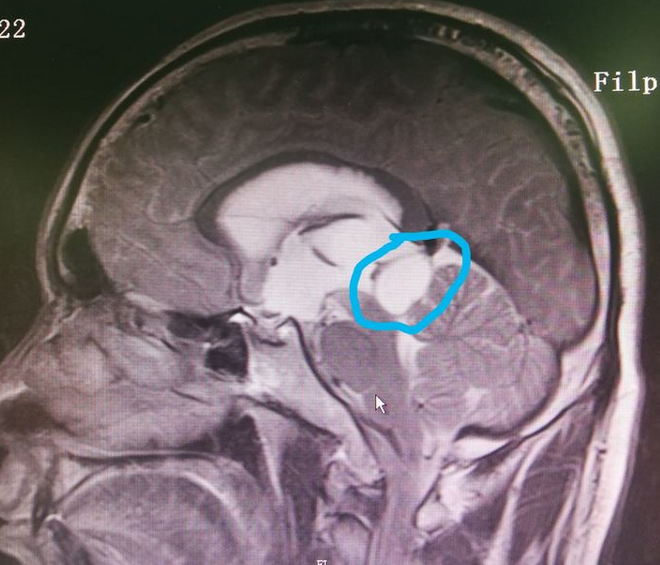

【省立影像读片】松果体区肿瘤 21.07

松果体区肿瘤

松果体区的巨大肿瘤